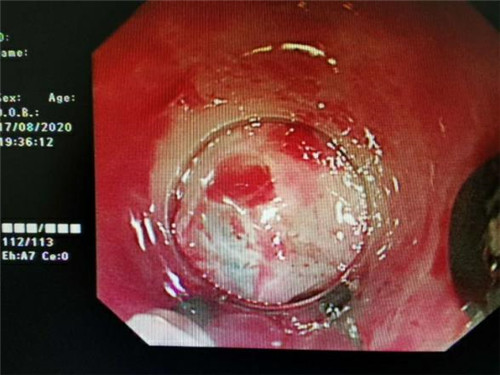

手术中,在镜下发现数条食管静脉曲张延伸至胃底,胃腔内有大量新鲜红色血液及血凝块,寻找到出血部位时仍在向外渗血,血压持续下降,患者时刻有生命危险。曹鹏副主任当机立断对曲张静脉破口处进行组织粘合剂及硬化剂注射,并对曲张静脉进行套扎治疗,在麻醉师陈琦的保驾护航下,整个过程不到半个小时,为患者成功止血,患者转危为安。